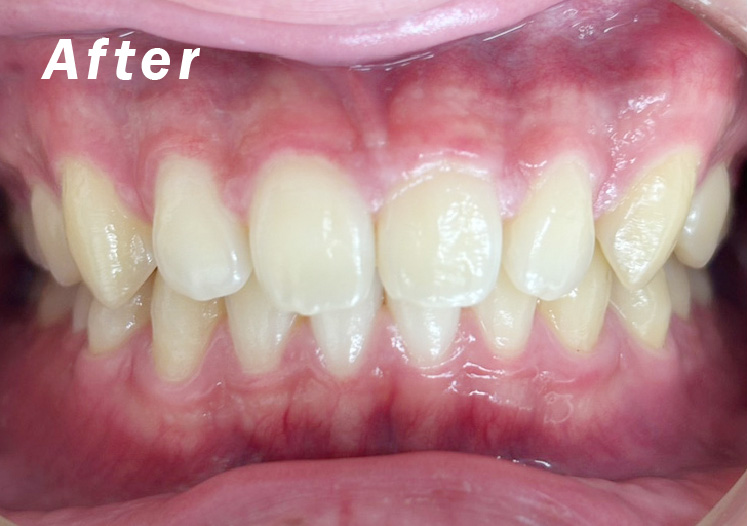

矯正after

矯正種類 ワイヤー矯正

症例 上下額叢生

治療期間 2021年12月〜2024年10月

性別/年代 男 13歳

治療費 748,000円

適切な時期に治療が開始できたので、歯並びだけでなく顎や顔貌も理想的に成長しました。歯磨きもしっかりできるようになりました。